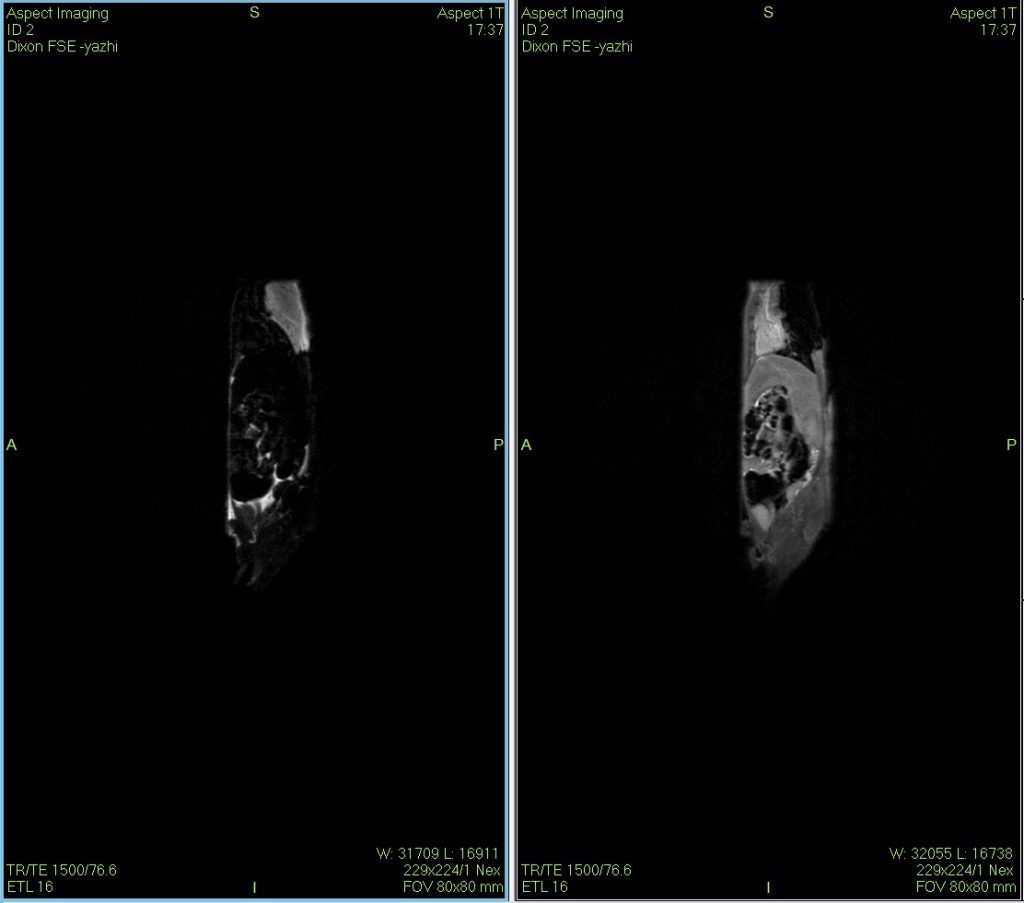

小鼠核磁共振Dixon水脂成像圖

Dixon水脂分離技術(shù)是一種使用的核磁成像技術(shù),在某些動物疾病模型的診斷、鑒別與治療過程的評估上具有一定的獨到之處。